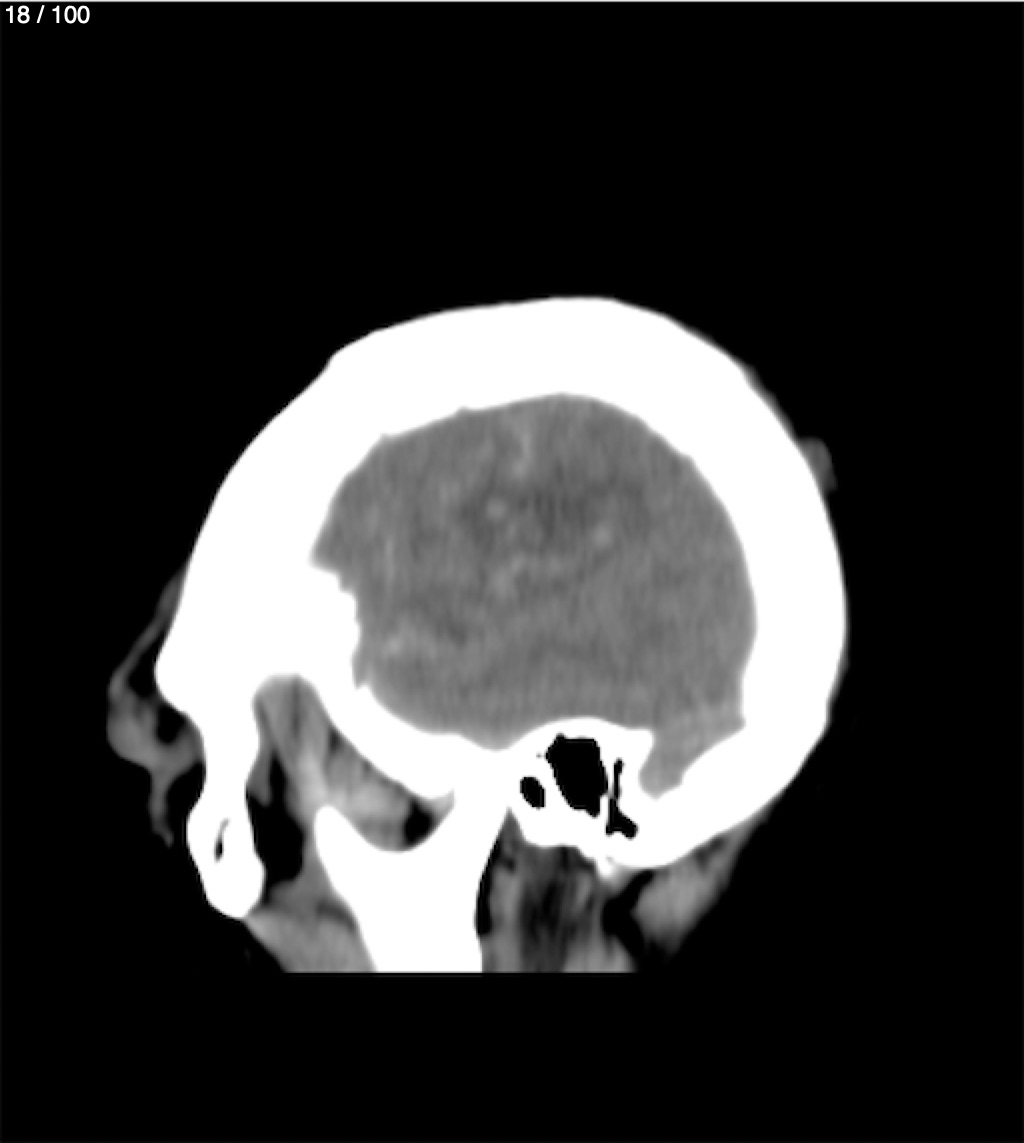

Maria Lopez Aguilar 78A - E+1 Tc Craneo